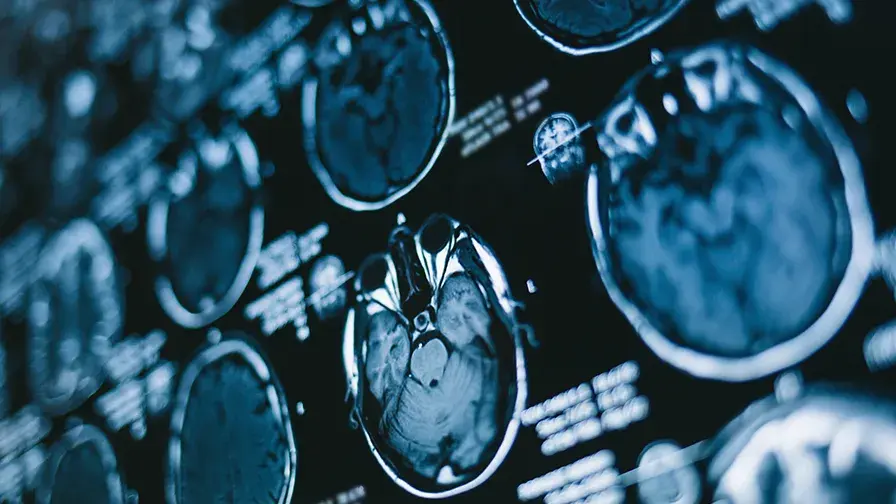

• IRM Cerveau

© Getty images